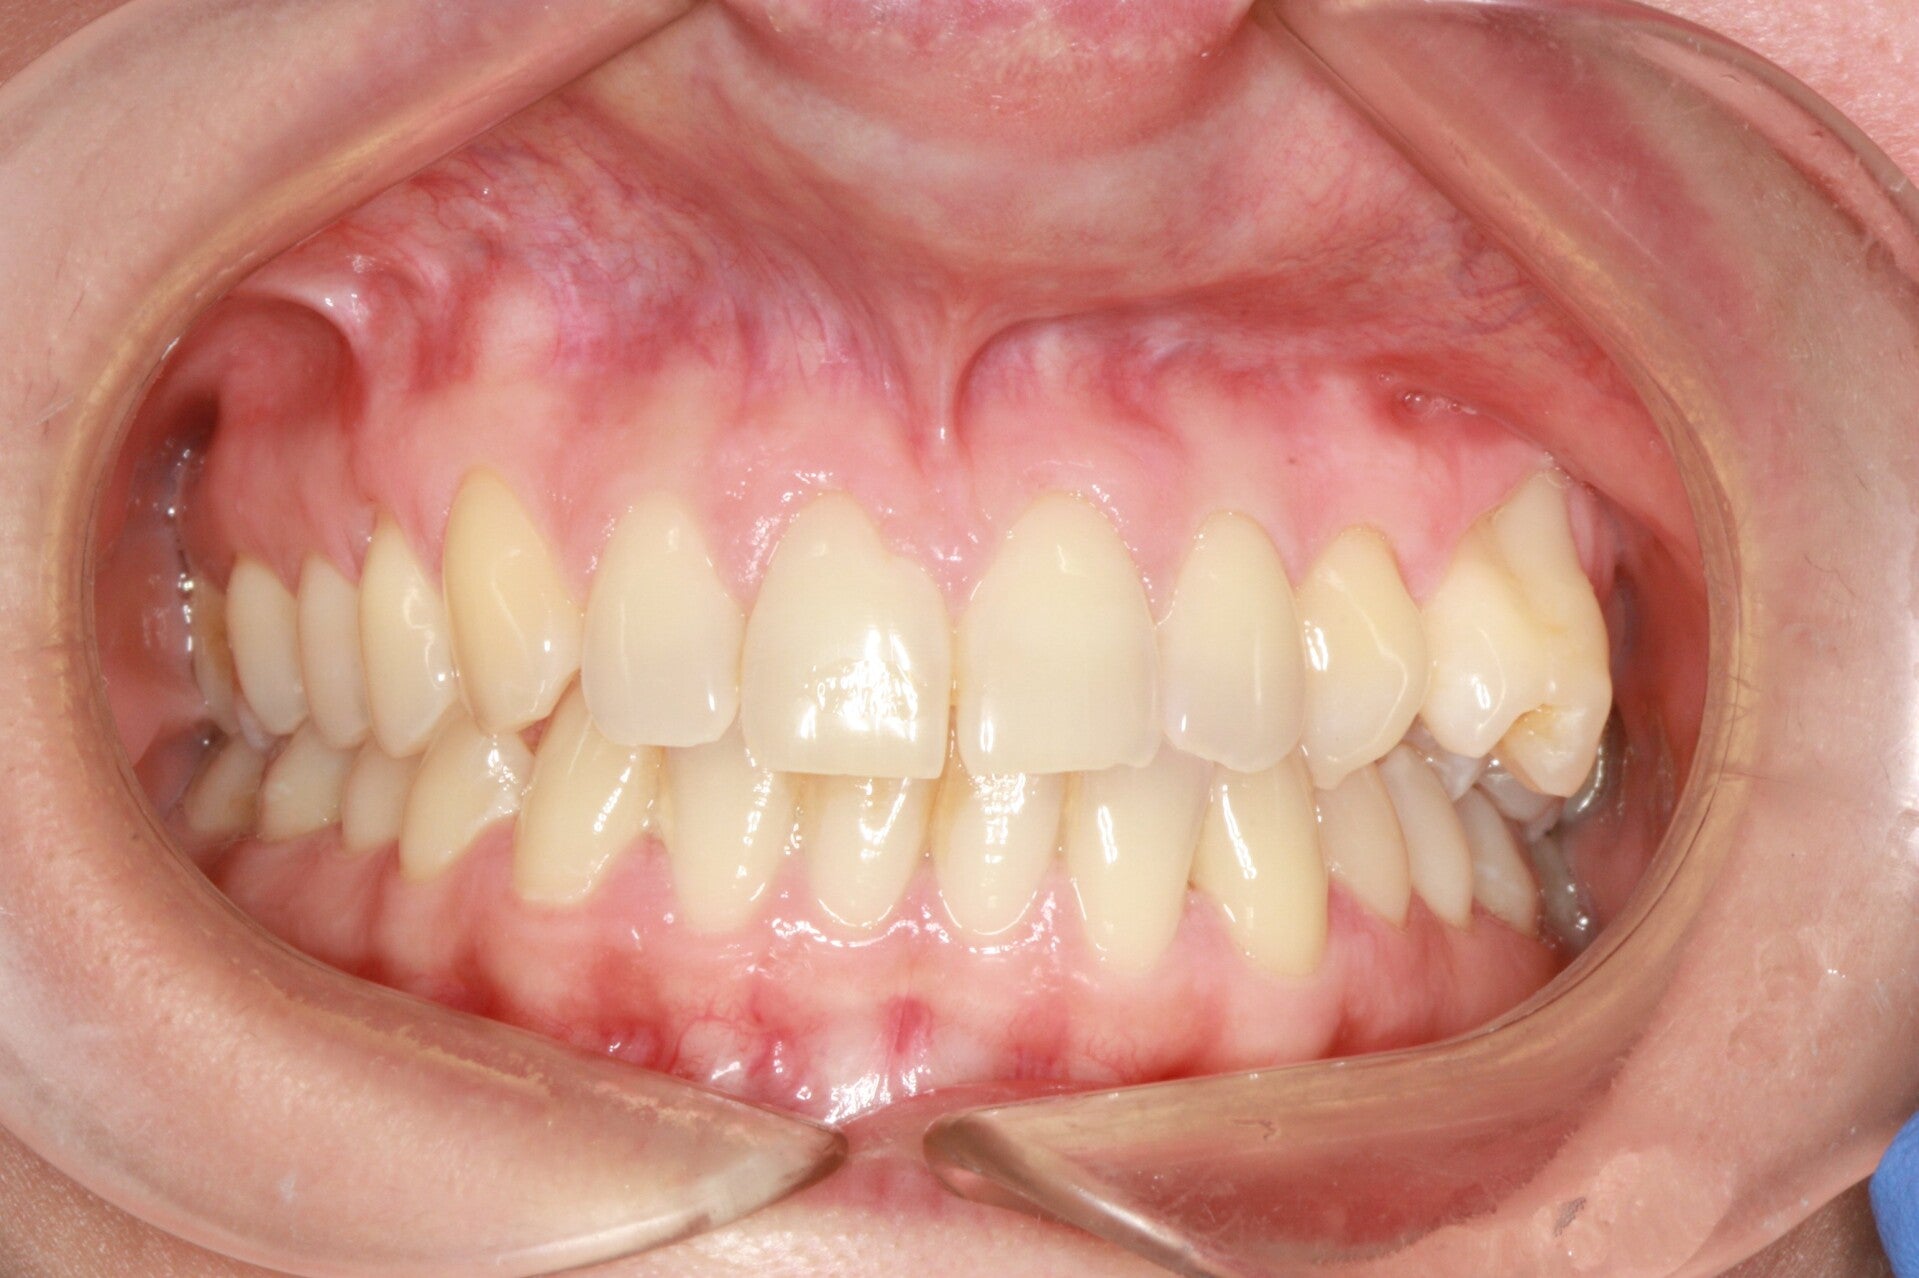

FOTO FINALI DOPO 24 MESI CIRCA DI TERAPA ORTODONTICA FISSA

Abbiamo appena portato a termine questo caso che presentava in arcata superiore il primo premolare di sinistra completamente fuori arcata sovrapposto al secondo premolare ed il canino ruotato.

in arcata inferiore invece abbiamo estratto il secondo molare di sinistra perso per carie deostruente e mesializzato il terzo molare in modo da chiudere lo spazio e non ricorrere all'inserimento di protesi implantare.